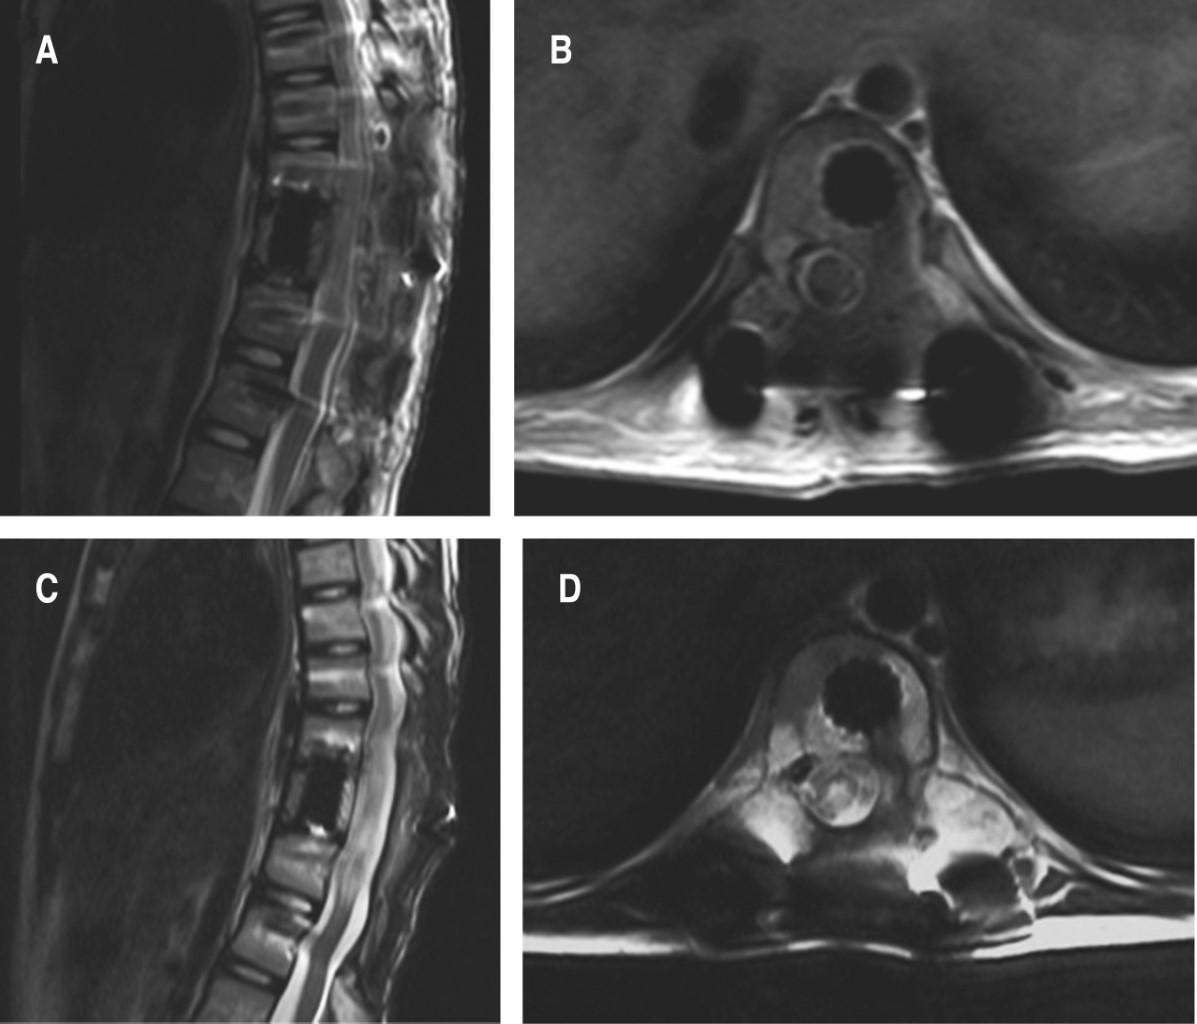

Dos semanas después reingresa a hospitalización, refiriendo lumbalgia, debilidad de extremidades inferiores y dolor abdominal secundario a realizar ejercicios de rehabilitación. A la exploración, paciente en silla de ruedas con dolor lumbar y abdominal difuso a la sedestación fuerza 1/5 de la escala de Daniels L2-S1 bilateral, disestesias en mismos niveles, signo de la navaja de muelle, hiperreflexia rotuliana y Babinski bilateral. Se realiza tomografía axial computarizada de cráneo y toracoabdominal, se identifica nivel de T10 lesión lítica que compromete hemicuerpo, pedículo y lámina izquierdos, con imagen sugerente de invasión parcial de conducto medular de predominio izquierdo (Figura 1). En la resonancia magnética nuclear simple de columna torácica se observa, en cortes coronal sagital y axial a nivel de T10, una lesión isointensa en T1 e hiperintensa en T2 de predominio izquierdo que compromete el conducto medular (Figura 2).

Se obtiene control postquirúrgico imagenológico con adecuada colocación de tornillos transpediculares y malla cilíndrica de titanio, en resonancia magnética simple se corrobora liberación del conducto medular sin cambio de intensidad de señal medular (Figura 3).

Se recaba reporte de patología con hemolinfangioma difuso compatible con la enfermedad de Gorham-Stout, el cual infiltra tejido óseo, médula ósea, tejido fibroadiposo y músculo estriado (Figura 4).